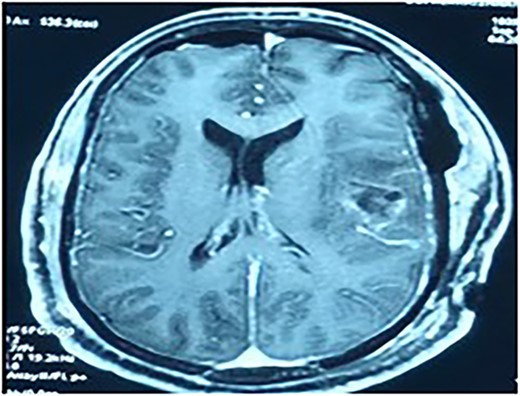

MRI brain with contrast revealed a heterogeneous irregular rim of an enhancing lesion with a size of 3.6 × 3.4 × 2.4 cm appearing in the left frontal subcortical region, with mild perilesional edema extending into the corona radiata and external capsule (Fig. 1). Due to an increased intracranial pressure, there was a mild midline shift of 5.3 mm toward the right side. Moreover, there was no evidence of intralesional hemorrhage or calcification seen.

MRI brain with contrast—a heterogeneous irregular rim of an enhancing lesion with a size of 3.6 × 3.4 × 2.4 cm appearing in the left frontal subcortical region, with mild perilesional edema extending into the corona radiata and external capsule.